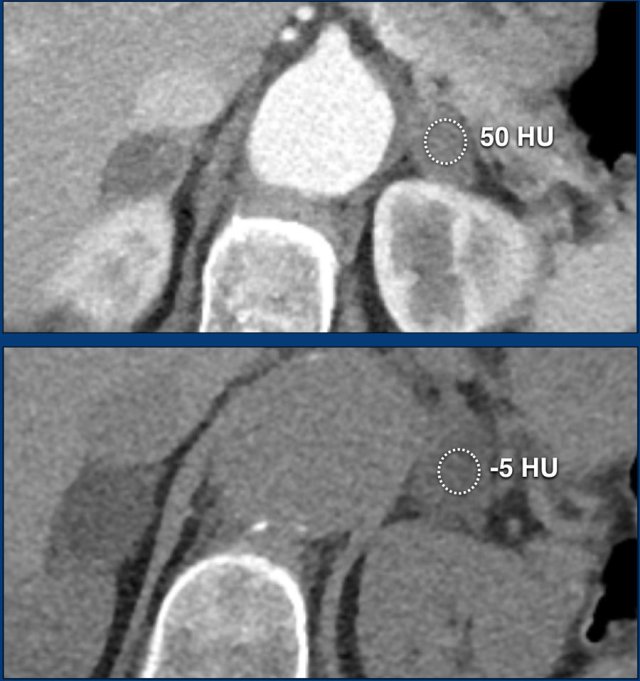

The images show bilateral adrenal incidentalomas found in a 64-year old patient scanned for analysis of an abdominal aneurysm.

The scan in the arterial phase shows bilateral lesions with a density of 50 HU.

On the non-enhanced CT performed a few days later, the density in both adrenal glands was less than 10 HU, proving these to be lipid-rich adenomas.